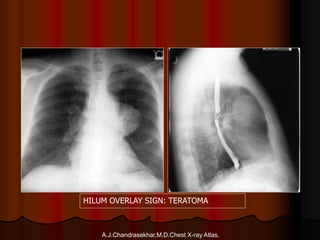

31-Oct-1435

A.J.Chandrasekhar,M.D.Chest X-ray Atlas.

HILUM OVERLAY SIGN: TERATOMA

Thymoma

Schwannoma